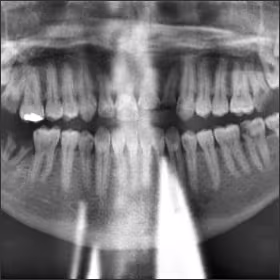

Panoramic radiographic imaging technique, error recognition, and error correction are the primary topics covered in this course. The optimal production of a panoramic image will be discussed including a step-by-step technique for acquiring a diagnostic image. Interpretation of the basic anatomic structures found on a panoramic image will be presented along with the identification and correction of imaging errors. Finally, a summary of common positioning errors will be provided to facilitate the assessment of unacceptable images incorporating key features of errors ranging from patient preparation to technical problems. This course is provided to enhance the participant’s understanding of common errors and their correction with the goals to improve image quality, reduce retakes, and decrease unnecessary ionizing radiation exposure to the patient.